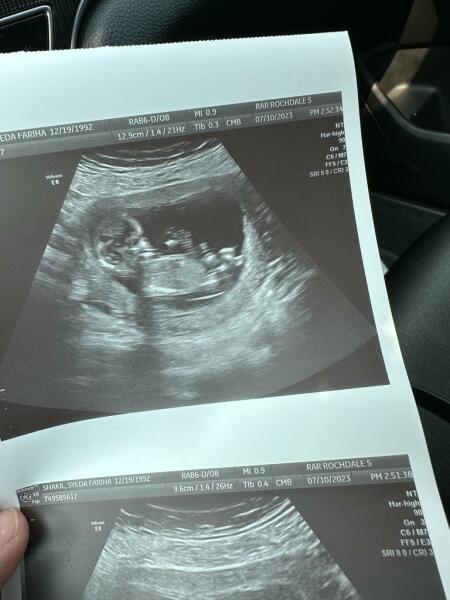

Fareeha1992 · 26/07/2023 22:14

Boy or girl 12 weeks

Skull theory